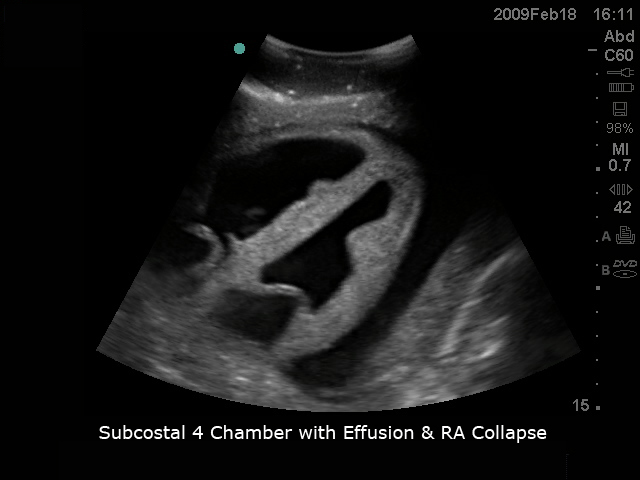

模型具有逼真的心脏解剖超声图像,从不同角度可进行经食道和经胸廓心脏20个标准切面探查及测量,同时可进行超声引导下心包穿刺的完整流程训练。